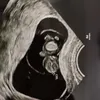

Potret Asmirandah Dirawat di RS Karena Keguguran, Makamkan Anak Keduanya di Bawah Tanaman Hijau

Asmirandah harus merelakan calon anak keduanya yang tidak bisa bertahan setelah dirinya terkena covid-19. Pada bulan ketiga hidupnya di dalam kandungan, jantung janinnya berhenti berdetak.

Dengan hati hancur, Asmirandah harus mengikhlaskan kepergian anaknya. Namun ia mendapatkan penghiburan dari anak pertamanya, Chloe yang selalu mendampinginya.

Asmirandah kini tengah berduka karena kehilangan calon anak keduanya. Namun Chloe, sang anak pertama selalu memberinya semangat.